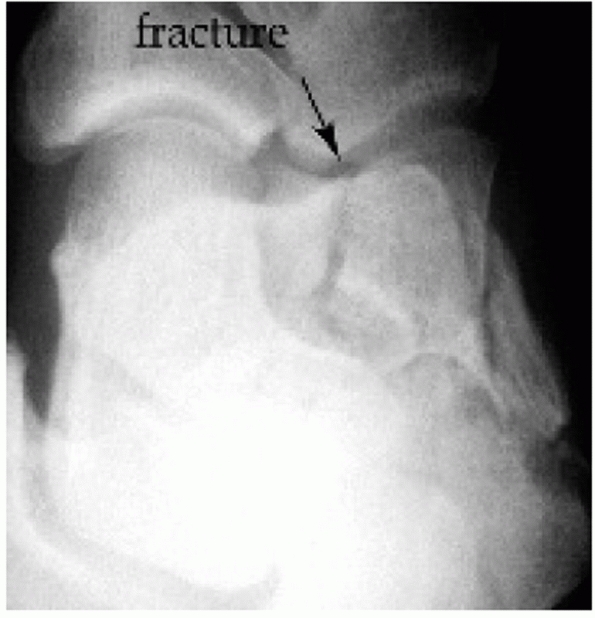

![]() |

FIGURE 59-19

True intra-articular tongue fracture (type IIB). Plain radiographs are unable to determine whether the fracture involves the posterior facet (A,B). Semicoronal and transverse CT scans verify intraarticular displacement (C,D). Note black arrows, indicating intra-articular fracture, and white arrows, indicating the intact lateral wall component typical of tongue fractures. |